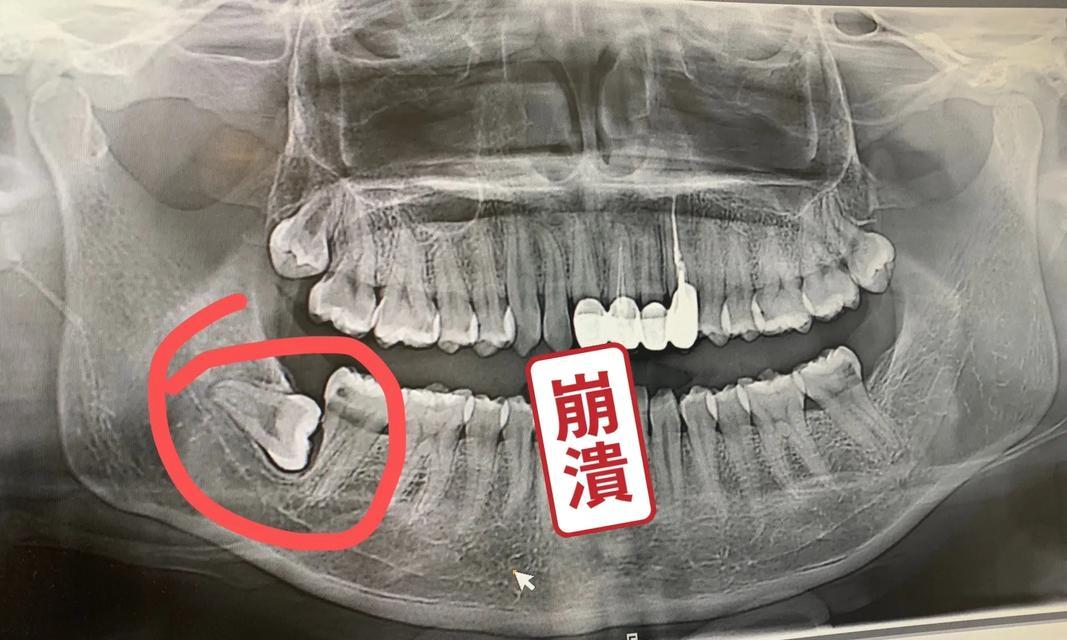

七、进行智齿X光检查

在决定如何拔除智齿之前,进行智齿X光检查非常重要。通过X光检查,牙医可以准确确定智齿的位置和形状,以便制定出最佳的拔牙计划。

二、智齿横生引起的智齿难拔

有时,智齿并不按照预期的方式生长,而是横生在其他牙齿的位置上。这种横生的智齿往往会受到周围牙齿的压力,导致无法正常生长,从而造成智齿难拔的情况。

三、智齿过度倾斜引起的智齿难拔

当智齿向周围牙齿倾斜生长时,也可能导致智齿难以拔出。过度倾斜的智齿会与其他牙齿产生摩擦和咬合问题,使其无法顺利脱落。